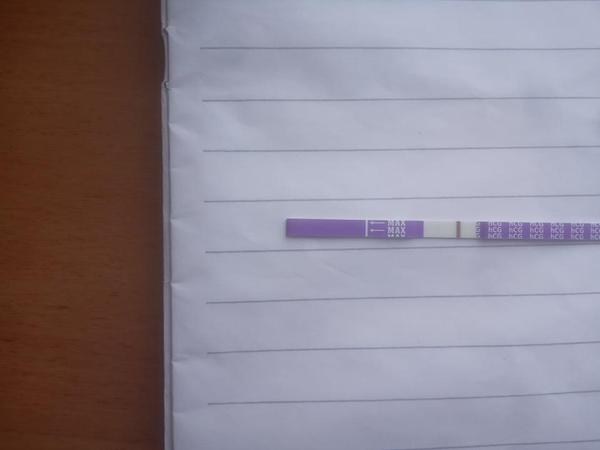

Test v den očekávané ms. Je to duch?

@rulexnone no krása gratuluji ♥ ♥ já dneska takto 😀 13 dnů od ovitrelle,12 dnů od IUI a 11DPO ♥ ve skutečnosti to už je reguální čárka ♥

@rulexnone asi taková jakou jsi měla včera ♥ ♥ ms mi nemá dojít za 3 nebo 4 dny ♥ ♥ ♥